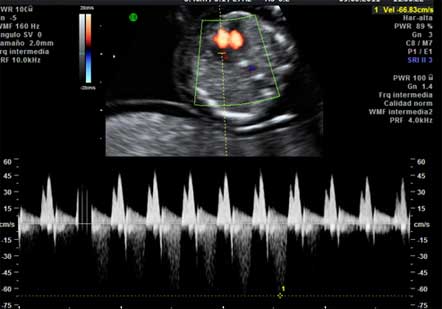

Translucencia nucal (TN) aumentada

Es un marcador tanto de cromosomopatías (síndrome de Down y otros) como de afectación cardiaca.